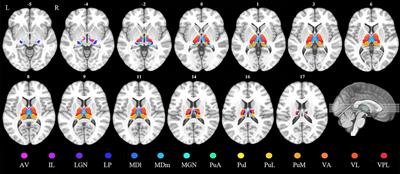

Volumetric assessment of individual thalamic nuclei in patients with drug-naïve, first-episode major depressive disorder

in Mood Disorders

- 3,894 views

- 11 citations